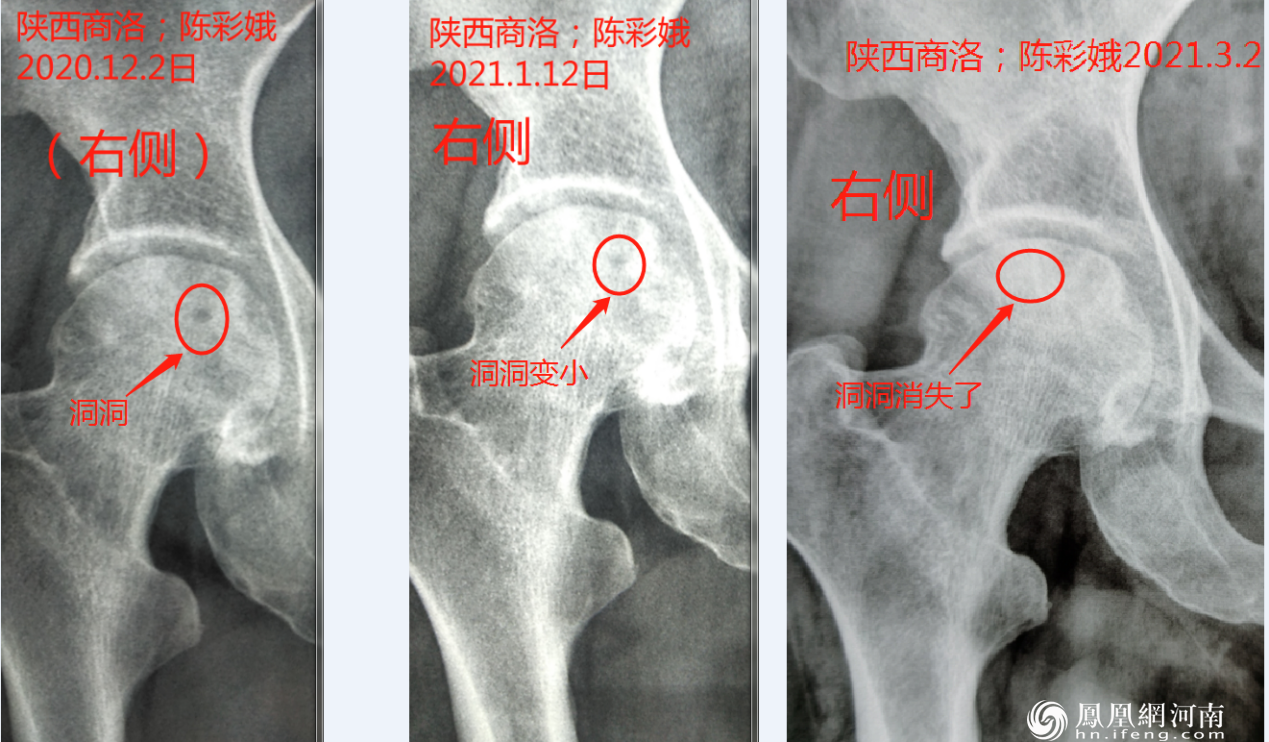

元一脊道“蒸敷灸”于2019年10月在河南济源开始利用纯理疗方法开展第一期中医‘“蒸敷灸”股骨头坏死临床试验,截止2021年五月将近六十余名患者参与技术临床试验,据对三期六十余名患者临床观察,三个月内缺血性骨坏死现象停止,骨小梁再生率达到百分之九十八以上,完全打破缺血性股骨头坏死不可改善与治疗的传统理论。

[骨科历史上首现股骨头坏死复活图片组]

(股骨头复活案例)用事实证明向世界证明:缺血性股骨头在中医“蒸敷灸”治疗下完全可以康复。

在“蒸敷灸”组合拳技术理疗下,患者康复时间大大缩短,三期以下基本都在三个月以将内病情完全控制,六个月内康复。众所周知,股骨一旦坏死不可能再生,业内也无法拿出一例股骨再生长的证据。“蒸敷灸”在临床的一年多来已经为世界医学界完成四十多套骨生长图谱。事实证明“蒸敷灸”技术不仅能使大部分股骨头坏死出现良好的骨修复,还能使部分塌陷股骨头隆起,治愈病人在很短时间到达骨头复原。

[首次骨科历史上股骨头坏死再重生图片组]